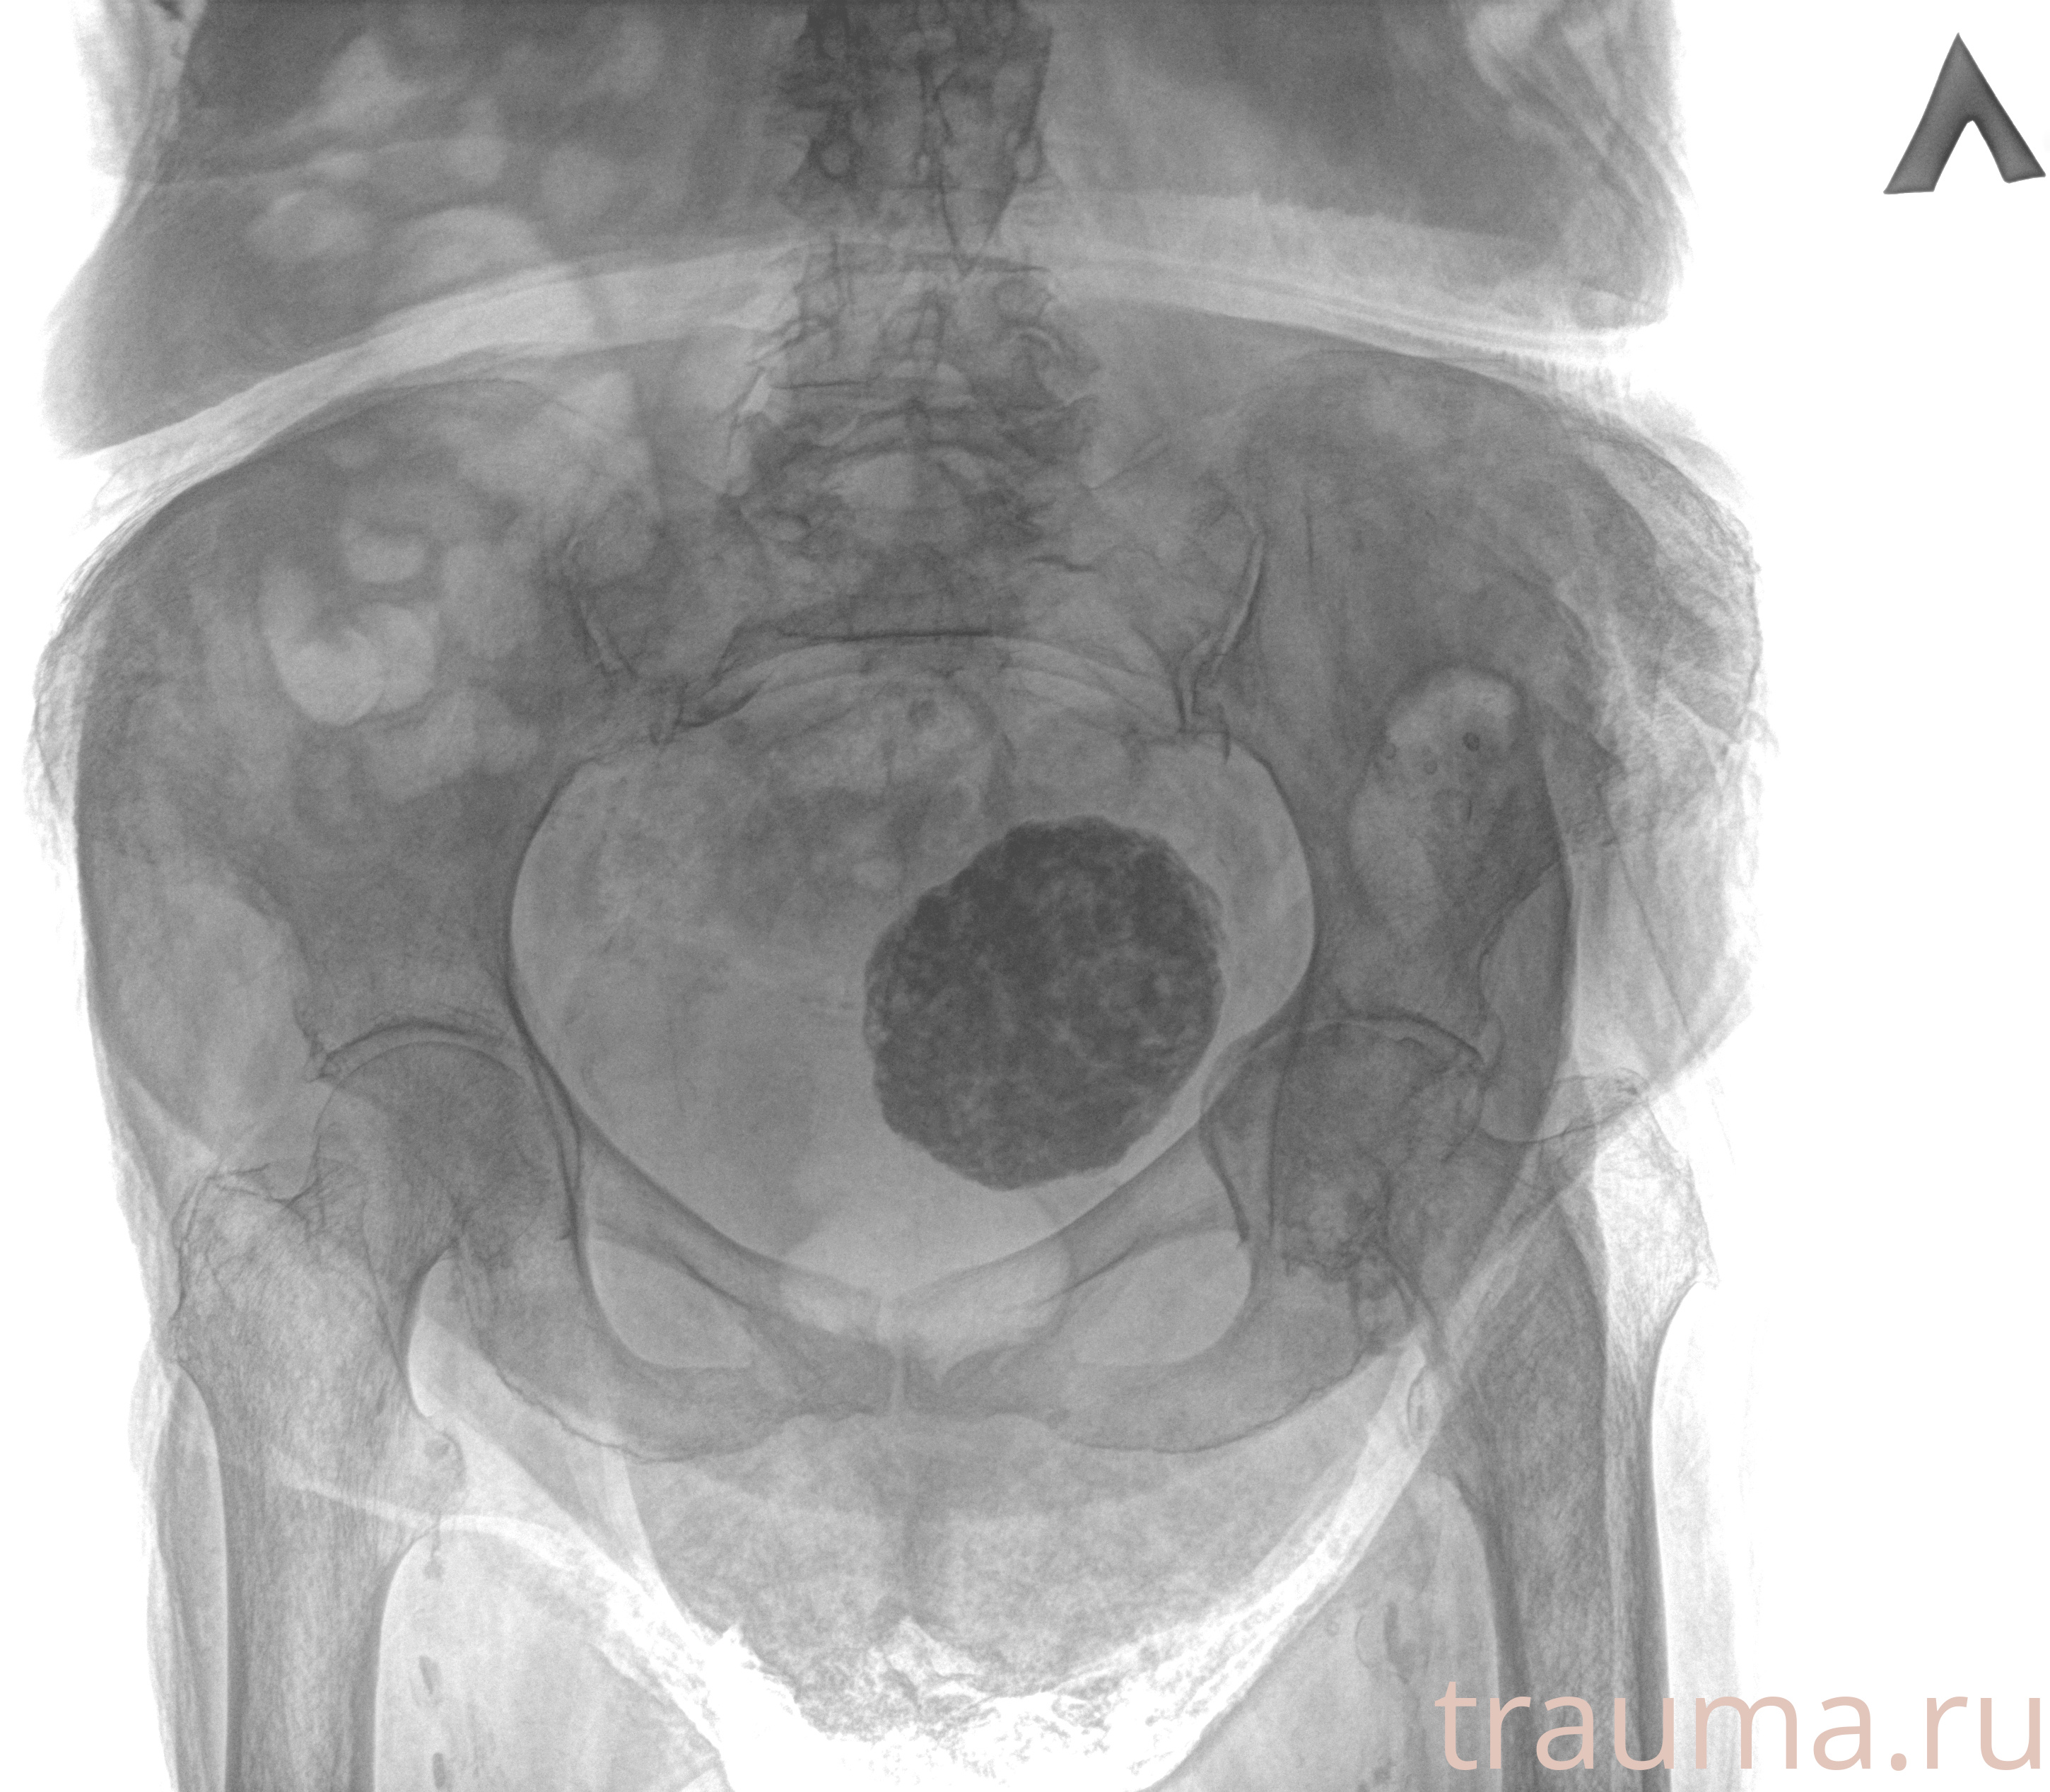

Рентгенограммы